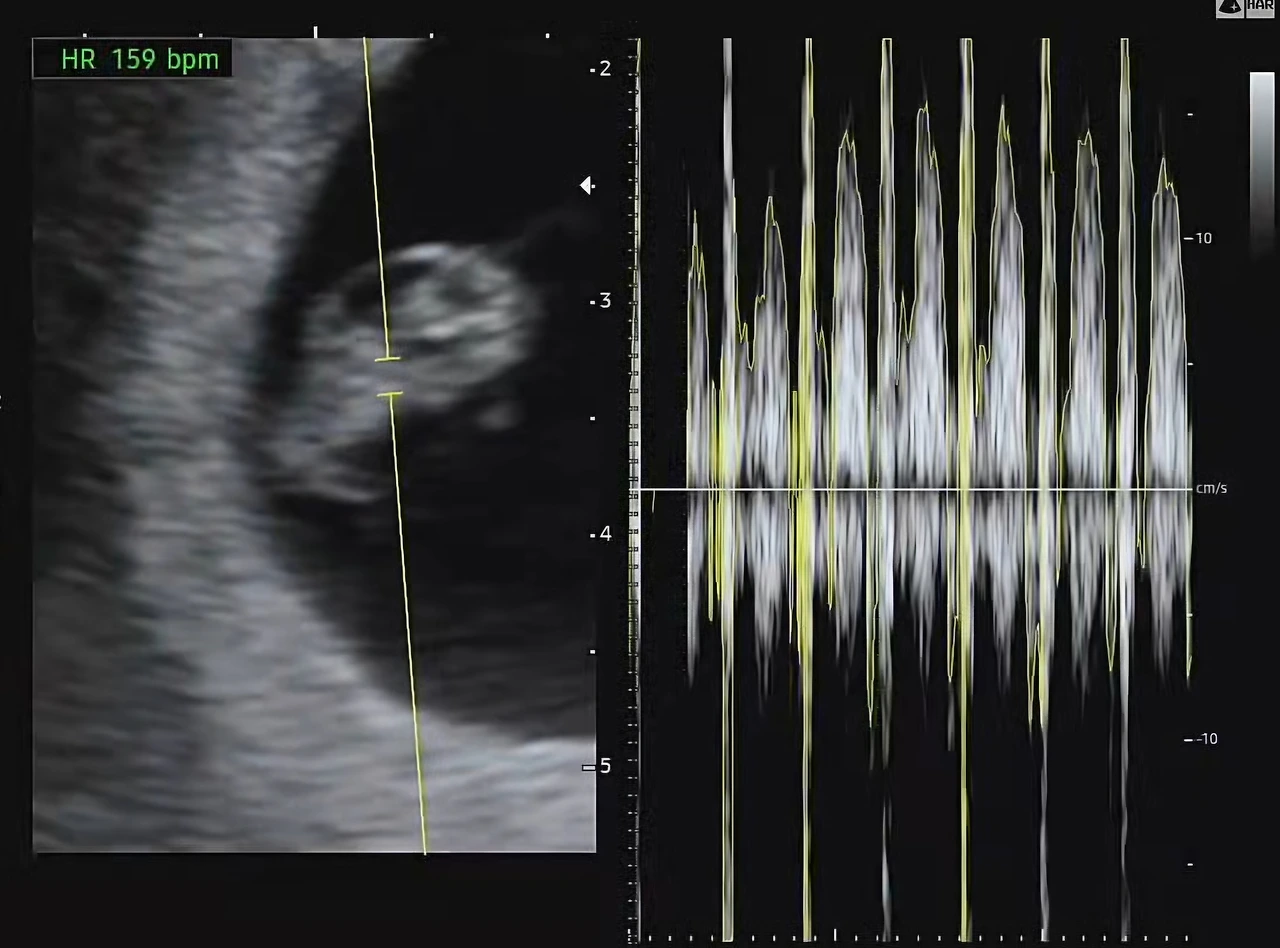

“이제, 심장 소리 들어볼게요.”

초음파 기계가 조심스럽게 초점을 맞췄고

그 순간, 초음파실 가득—

‘쿵쾅, 쿵쾅, 쿵쾅, 쿵쾅, 쿵쾅, 쿵쾅——’

단단한 무언가가 내 안을 두드렸다.

콩알만 한 심장이,

온몸으로 이 세상에 존재를 알리고 있었다.

소리는 마치 북소리 같았고

시간이 느리게 흐르는 것 같았다.